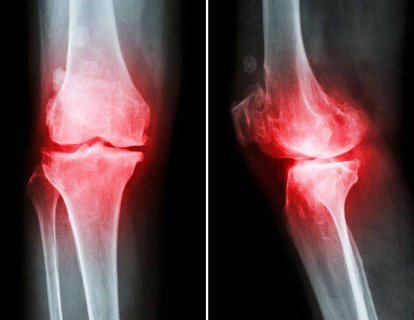

Osteoartrit kadınlarda en sık görülen eklem rahatsızlıklardan biridir. Şu ana